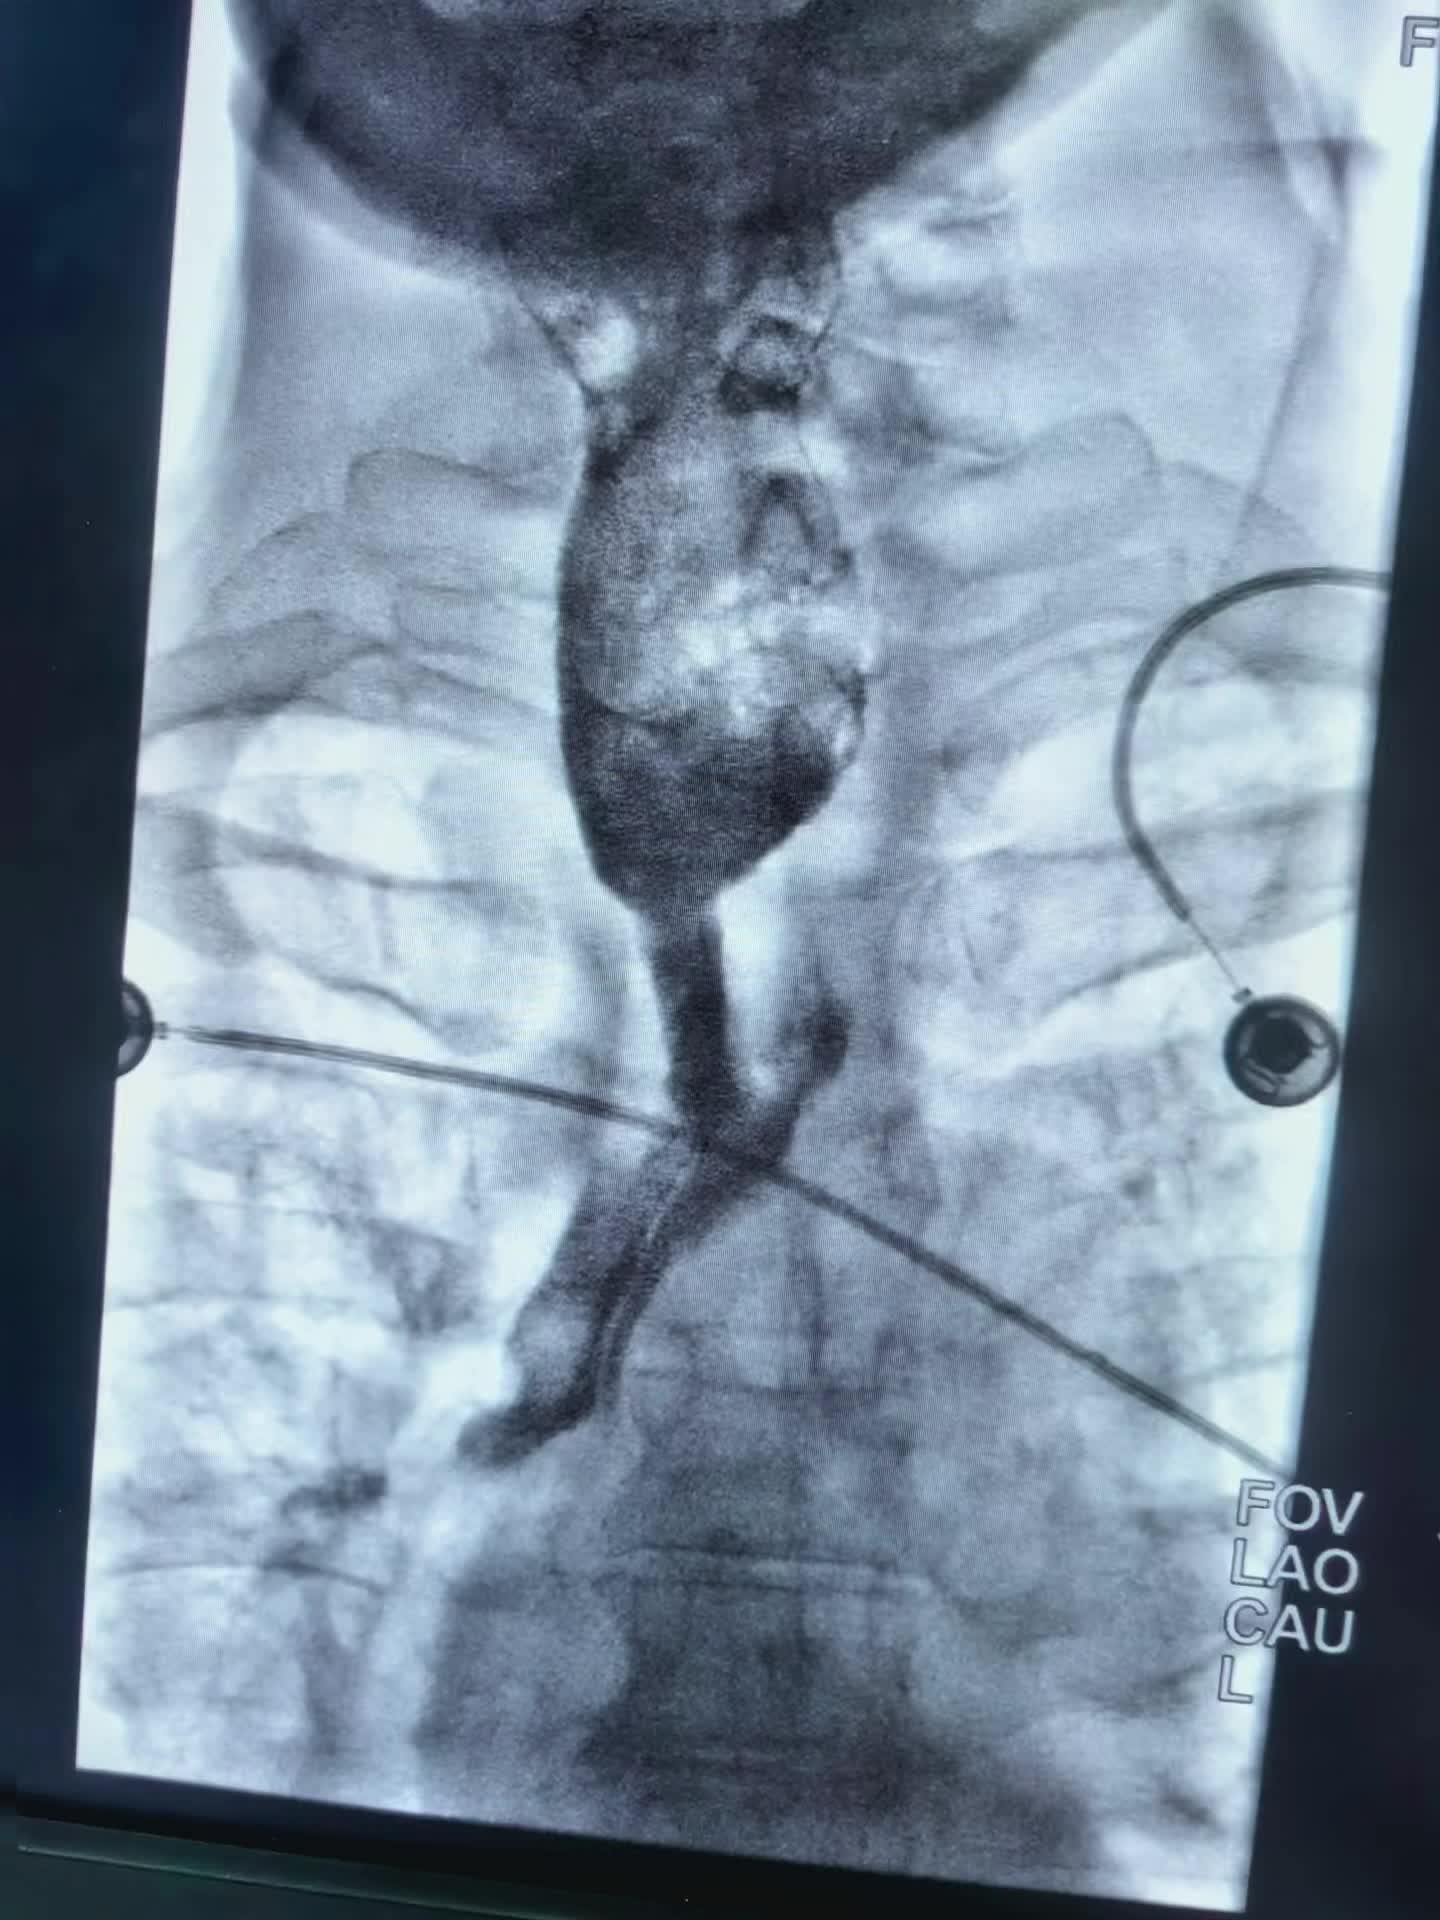

上午第一台78岁老年男性贲门癌患者,突发食管梗阻不能进食水,行球囊扩张,食管支架置入术,术即可恢复饮食。 第二台:食管癌术后3年再次进食哽咽,食管吻合口狭窄伴肠管膈肌处狭窄。单纯行球囊扩张术,术后即可恢复正常饮食。